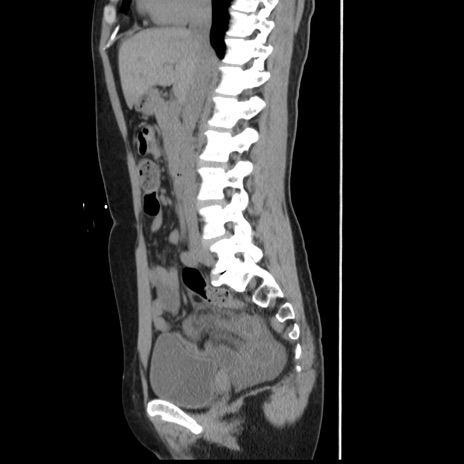

横断像

【症例】 50歳代女性

【主訴】 腹痛

【現病歴】前日生レバーを食べた。今朝に排便あり。 昼前に突然発症の腹痛を生じ、当院救急外来を受診した。

【既往歴】 子宮筋腫にてで子宮全摘後

【身体所見】 意識清明、腹部:平坦、軟、下腹部やや左を中心に圧痛・反跳痛あり、筋性防御あり

【データ】WBC 7800、CRP 0.07